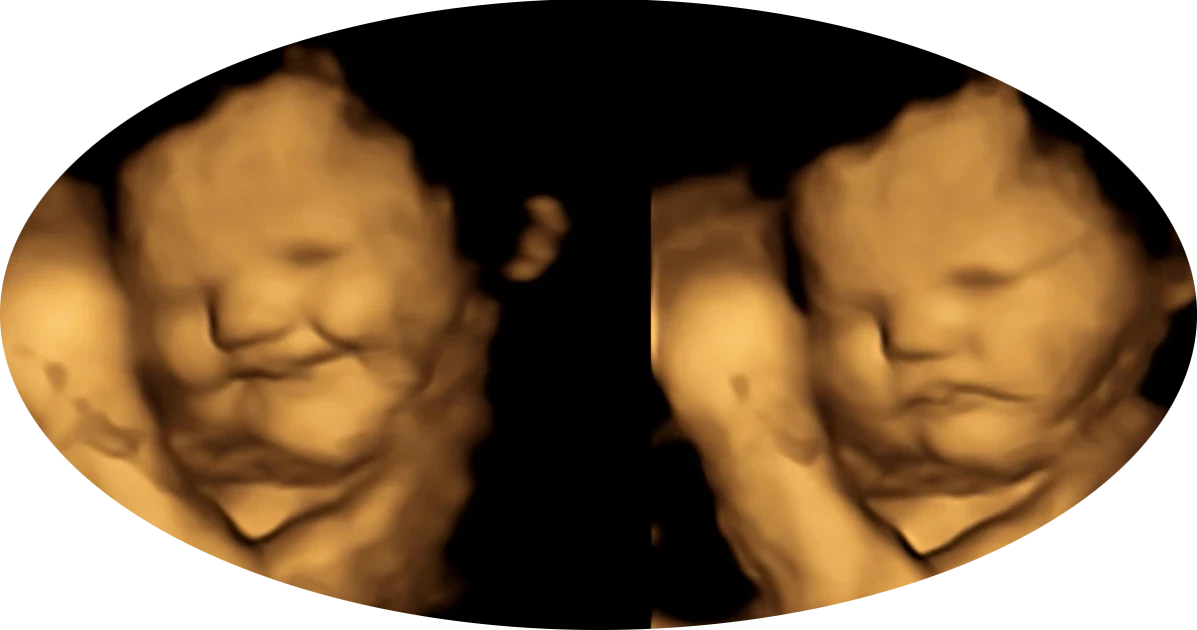

What do we see on 4D ultrasounds?

Research (including University of Durham, 2008) shows:

Babies start making facial expressions from around week 24-28

They can frown, yawn, and ‘laugh’

Smiling faces are usually seen in the third trimester

The images are so clear that parents and sonographers often say: “He/She is smiling!”